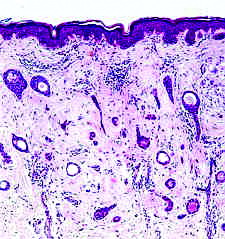

รอยโรคที่คล้ายสิวเหล่านี้มีลักษณะทางจุลพยาธิวิทยาที่แตกต่างกัน เช่น ใน syringoma พบเนื้องอกในส่วนบนของชั้นหนังแท้ ลักษณะเป็นท่อเล็กๆ ที่มีผนังเป็น epithelial cells หนา 2 ชั้น ดูคล้ายลูกอ๊อด (tadpole-shape) (ภาพที่ 21), ใน trichoepithelioma พบกลุ่มของเซลล์คล้ายเซลล์ชั้นฐานของหนังกำพร้า (basaloid cells) และพบซิสต์ที่ภายในเป็นเคอราติน (horn cysts) (ภาพที่ 22). ส่วน adenoma sebaceum นั้นเป็นชื่อที่ตั้งผิด (misnomer) เพราะลักษณะทางจุลพยาธิวิทยาที่แท้จริงเป็น angiofibromas.

ภาพที่ 21. จุลพยาธิวิทยาของ syringoma ภาพที่ 22. จุลพยาธิวิทยาของ trichoepithelioma